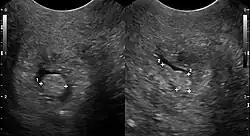

| Cervical polyp on ultrasound | |